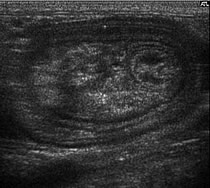

| Two examples of Intussusception |